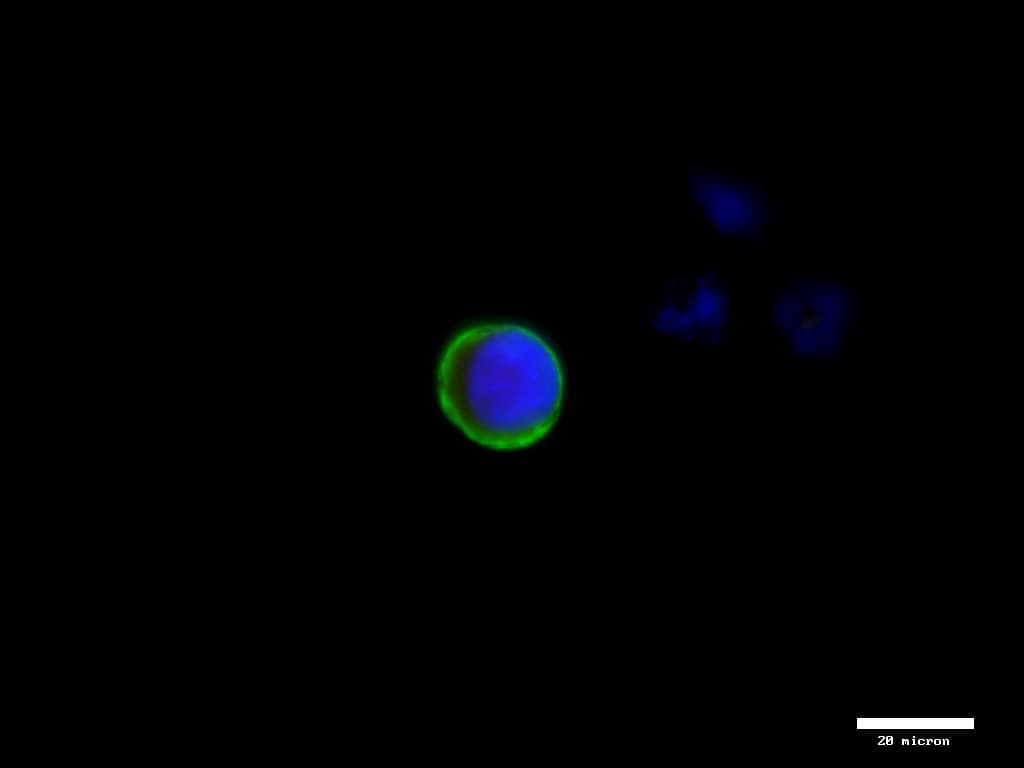

Example images from patient blood samples

CK + CTC from breast cancer patient (40x)